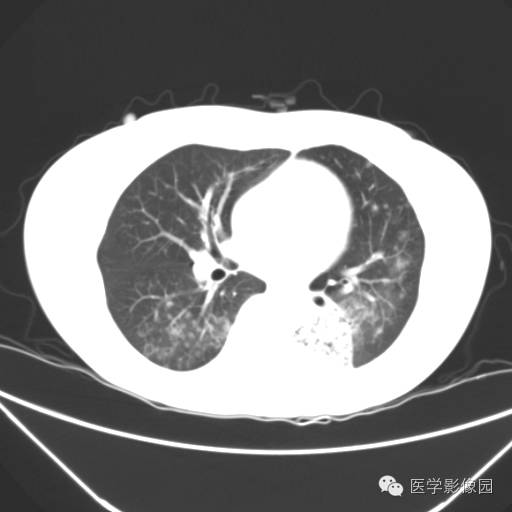

肺叶实变性支气管肺泡癌1例CT影像表现